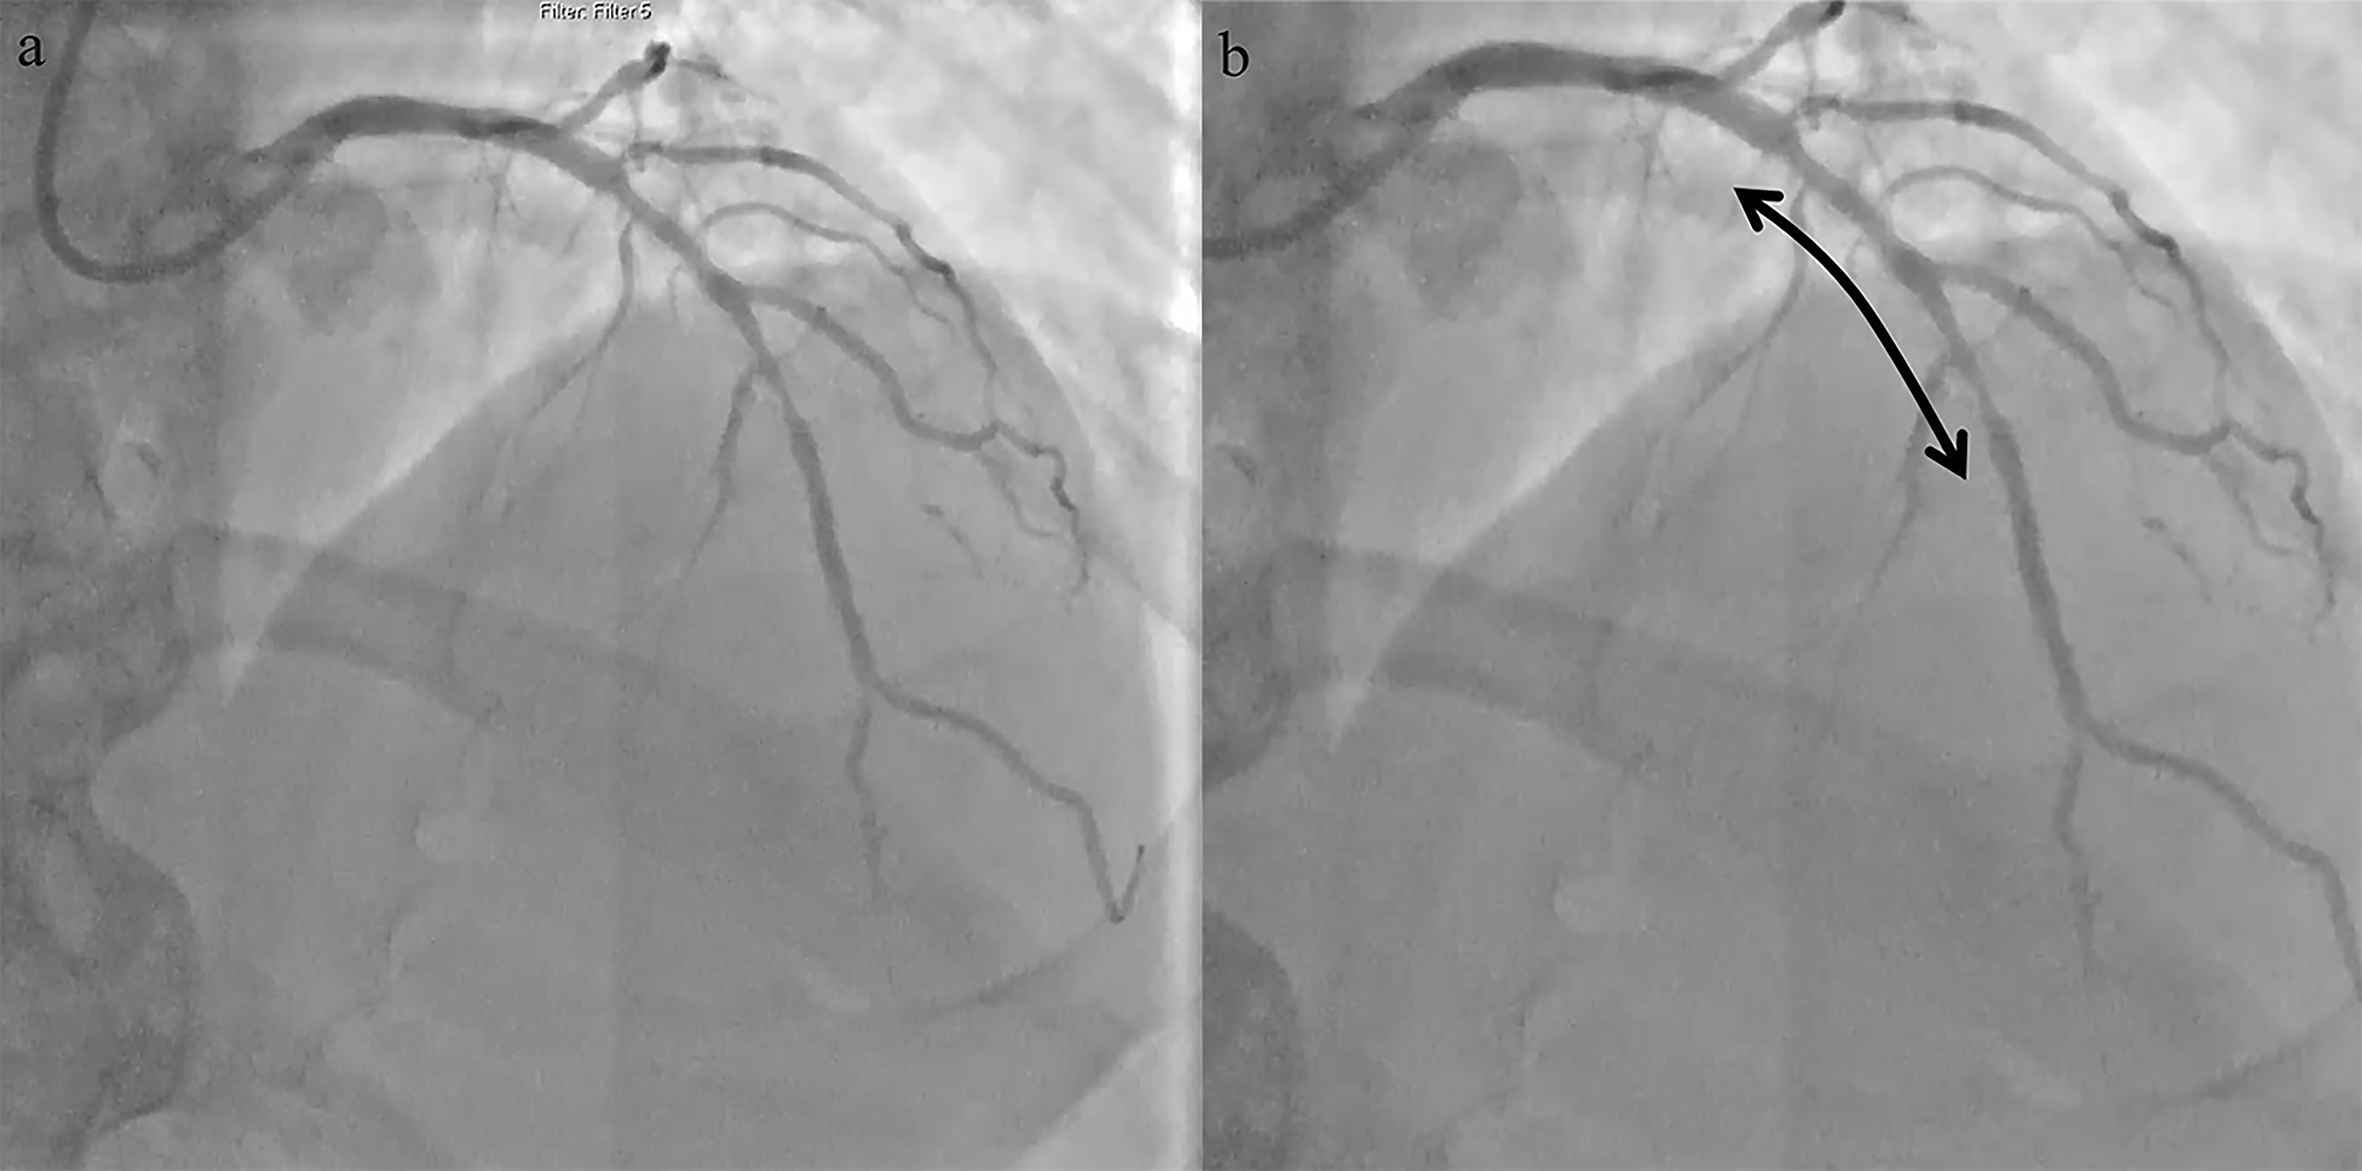

with 300 mg of clopidogrel prior to the procedure. The calcified lesion failed to

yield with conventional non-compliant balloons (Fig. 2). High pressure inflation

resulted in bursting of a 3.5 mm non-compliant balloon (Fig. 3). Intravascular

Fig. 2.Fluroscopic image showing the inability to prepare the lesions. (a,b) Using non-compliant balloons (2.5 mm and 3.0 mm) at high-pressures giving rise to dog-bone appearance (shown by the arrows). (c) Burst of a 3.5 mm non-compliant balloon when inflated at high-pressure (20 atm) with escape of contrast into the distal LAD and diagonal (shown by the arrows).